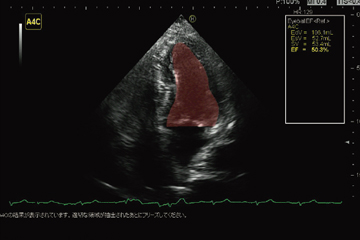

5.EyeballEF

循環器エコーにおいて,心尖部四腔断層像と二腔断層像との識別,およびその左室内膜の認識をリアルタイム画像解析することで,EF(ejection fraction)計測を行うことが可能な技術である(図5)。フレーム選択やトレース操作が半自動化されているため,ワークフローの向上が期待できる。